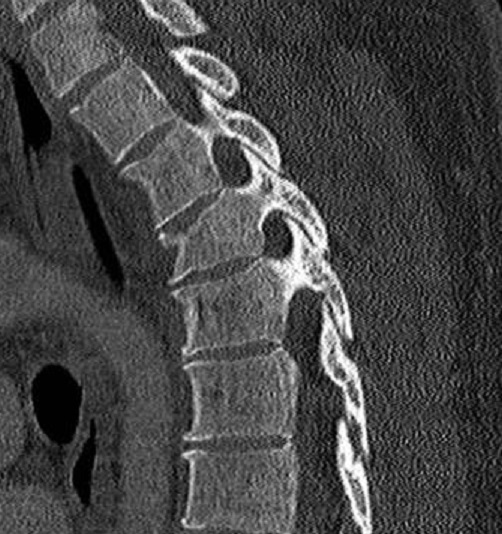

Même cas en coupe sagitale .

Ce qui nous donne de image de fracture en

association du D3 , D4 de la colonne vertebrale .

Au dessus de 50% des

cas de fracture du sternum avaient en association avec

des autres fractures avec mortalité peut elevé |